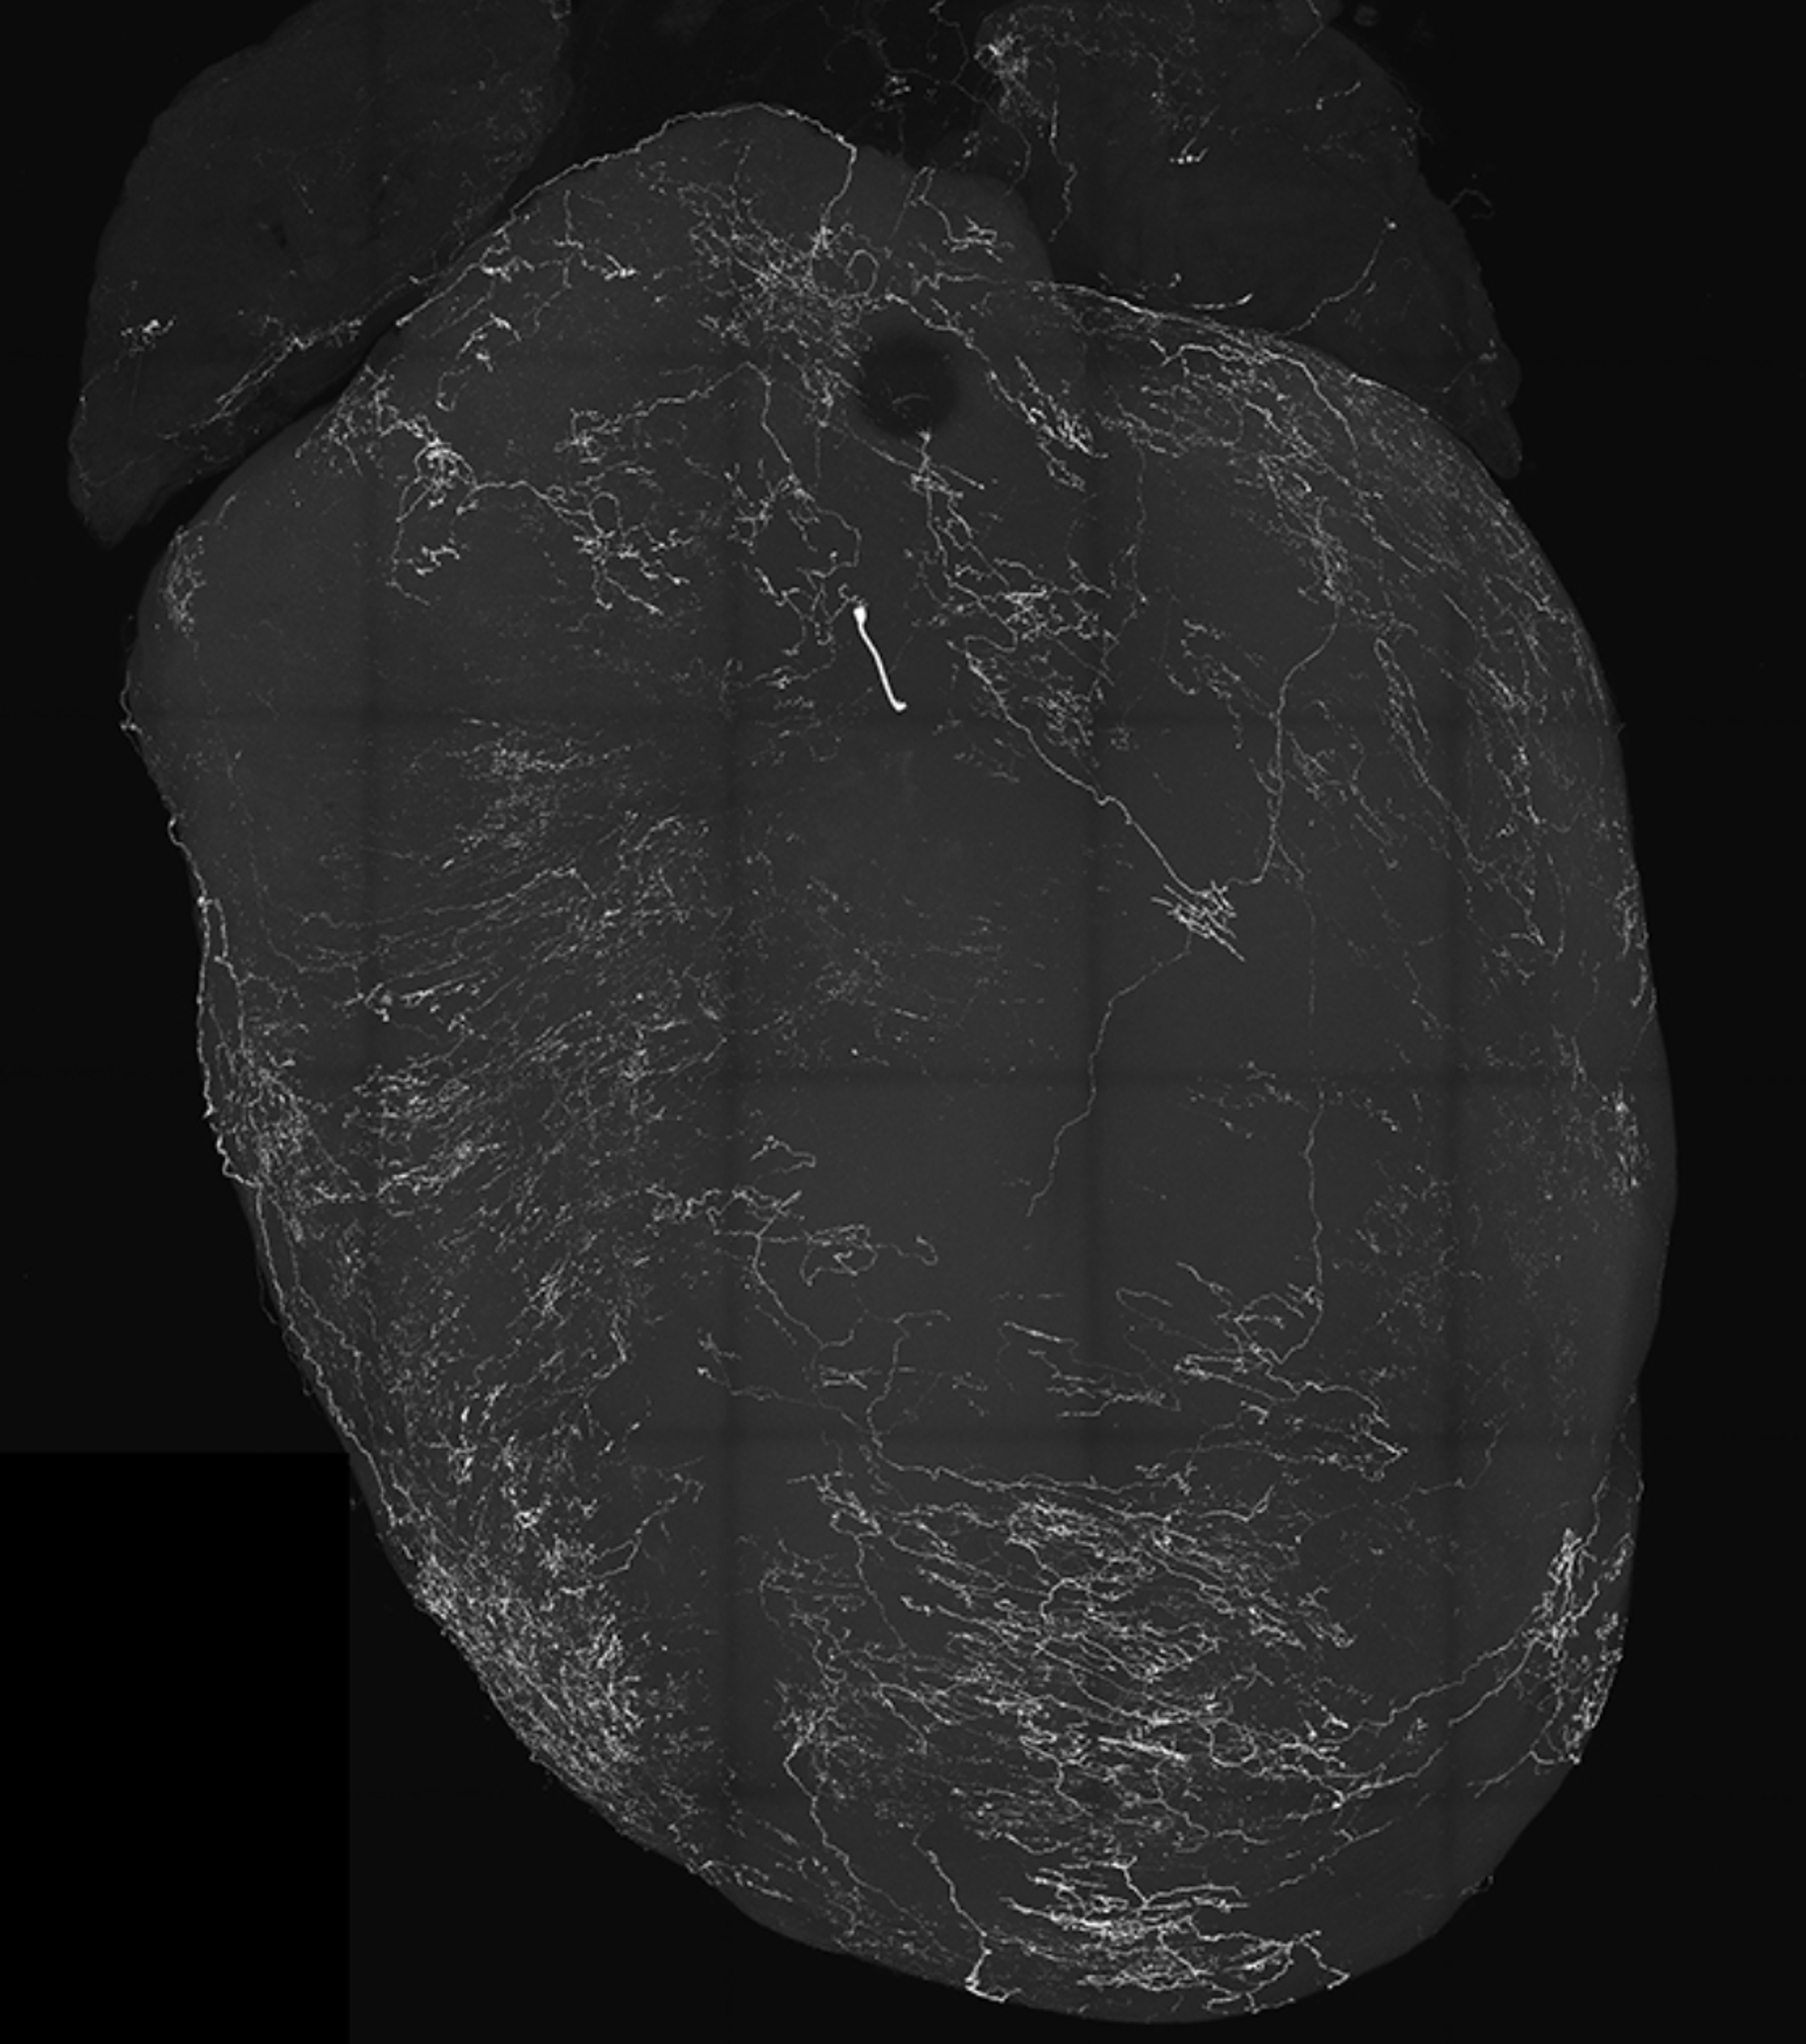

由迷走神经感觉神经元标记的心脏图像,迷走神经感觉神经元会引发晕厥 图/加州大学圣地亚哥分校奥古斯丁实验室